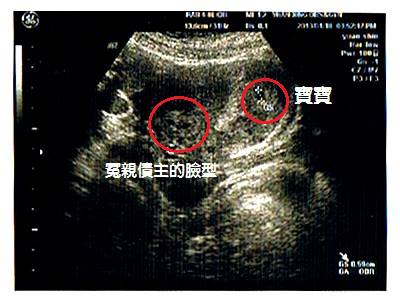

(圖)信眾第一次產檢時所拍的超音波照片,

有拍到冤親債主的臉型照。